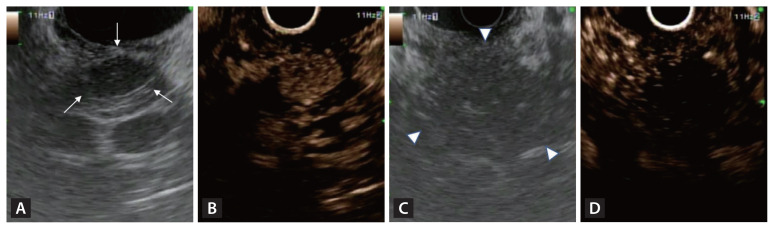

诊断技术的进步导致胰腺神经内分泌肿瘤(PNETs)的检测得到改善,从而增加了报告病例的数量。内镜超声(EUS)技术,包括与对比增强谐波成像的结合,有助于区分PNETs与其他肿瘤,而EUS引导的细针穿刺或活检提高了肿瘤的组织学诊断和分级。最近引入的eus引导下的乙醇注射或射频消融为PNETs的治疗提供了一种替代手术的方法。与手术比较显示出相似的结果,但副作用更少。尽管标准化的方案和长期随访的前瞻性研究仍然需要,但基于eus的方法是有希望的方法,可以有助于改善PNET患者的生活质量。

Advancements in diagnostic technology have led to the improved detection of pancreatic neuroendocrine tumors (PNETs) and thus to an increase in the number of reported cases. Endoscopic ultrasound (EUS) technology, including in combination with contrast-enhanced harmonic imaging, aids in distinguishing PNETs from other tumors, while EUS-guided fine-needle aspiration or biopsy has improved the histological diagnosis and grading of tumors. The recent introduction of EUS-guided ablation using ethanol injection or radiofrequency ablation has offered an alternative to surgery in the management of PNETs. Comparisons with surgery have shown similar outcomes but fewer adverse effects. Although standardized protocols and prospective studies with long-term follow-up are still needed, EUS-based methods are promising approaches that can contribute to a better quality of life for PNET patients.